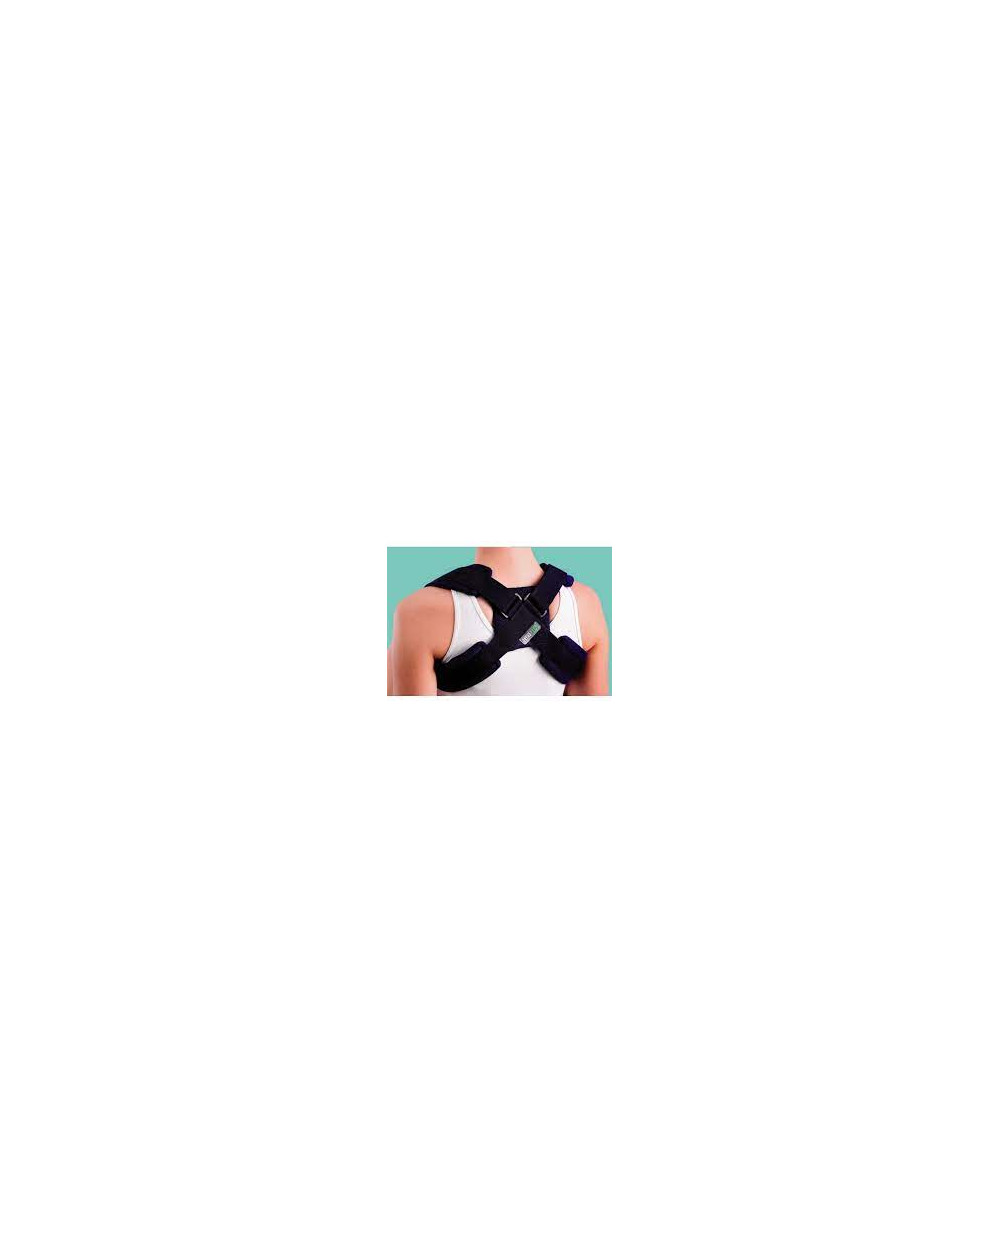

Sangle claviculaire

Indications :

Fractures claviculaires

Entorses acromio-claviculaires

Effets :

Un soutien claviculaire pour un maintien qui élimine la fatigue musculaire et aide à réduire les tensions tout en soutenant la clavicule.

Avantages :

légère lors du port grâce à sa forme anatomique, un grand confort d’utilisation avec une facile mise en place avec un système d’attaches dorsales auto-aggrippantes réglables.